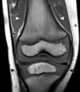

Hematopoietic bone marrow defect